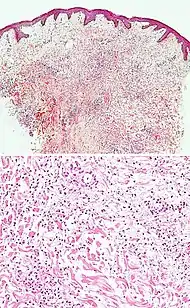

Neutrophilic infiltrate

| Dermatitis herpetiformis |

|

![]() |